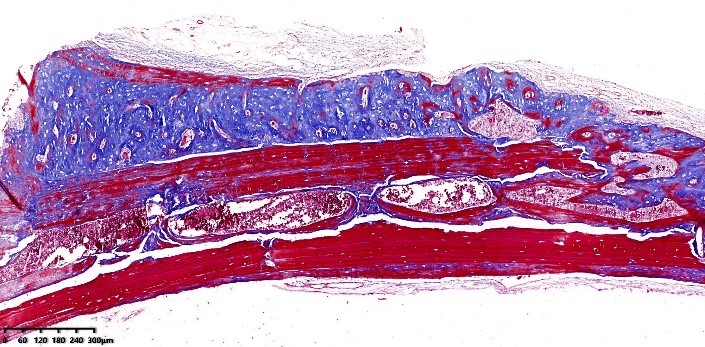

2、Masson染色实验结果(兔肌腱、大鼠股骨、大鼠皮肤、举例)

Masson染色实验解读:图片结果呈现胶原纤维蓝色,肌纤维红色,细胞核紫蓝色。